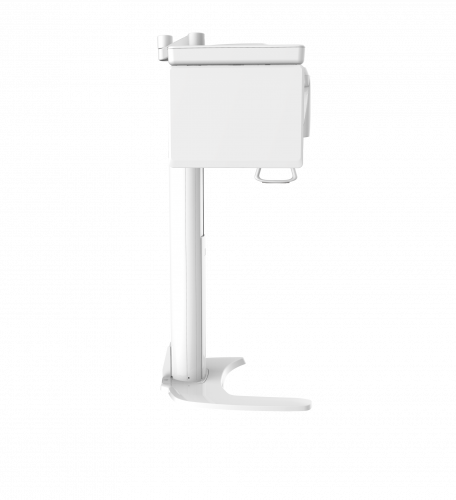

| TYPE | TOP VIEW | FRONT VIEW |

|---|---|---|

|

PaX-i (Pano) |

|

|

|

PaX-i SC (Pano/Scan Ceph) |

|

|